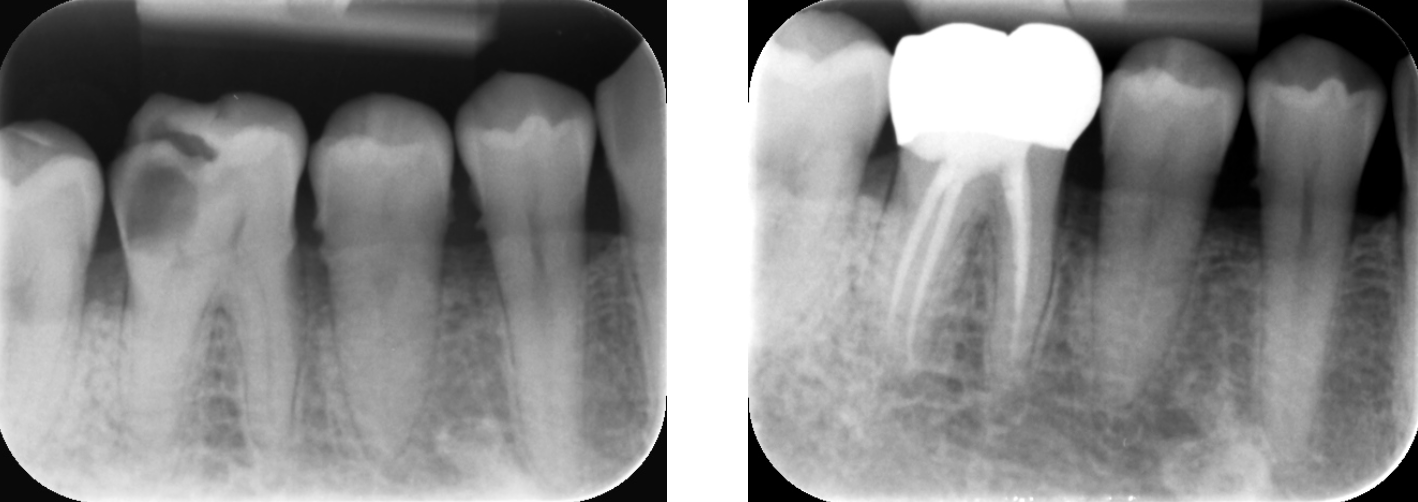

歯科用CTとは一般の医療用CTを歯科治療用に特化した装置です。

当院ではこの歯科用CTを使用して三次元で歯の構造を把握します。

任意の角度や位置から歯・顎骨を確認することもできるので治療の精度が大幅に向上します。